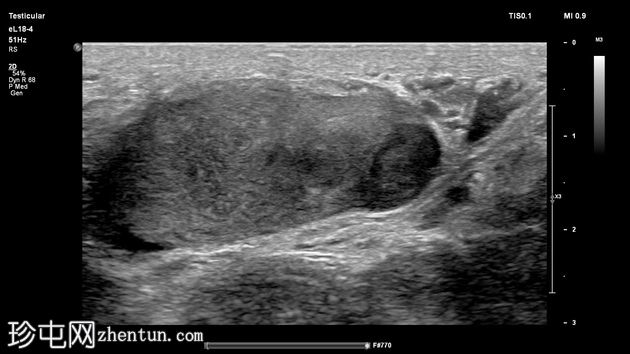

右侧阴囊内可见光滑的卵圆形高回声肿块,呈分层状,并伴有进行性声影,符合完整的睾丸假体。

左侧睾丸回声不均匀,可见边界不清的低回声区域,呈地图状分布,实质内散在分布着少量点状彗尾伪影,每个视野少于5个,符合局限性睾丸微石症。

睾丸下极可见一个边界清晰的卵圆形低回声结节,内部可见血流信号。大小为12 x 7 x 15 mm,高度符合睾丸肿瘤影像学表现。

可疑病灶旁可见边缘不规则的异常低回声区域。